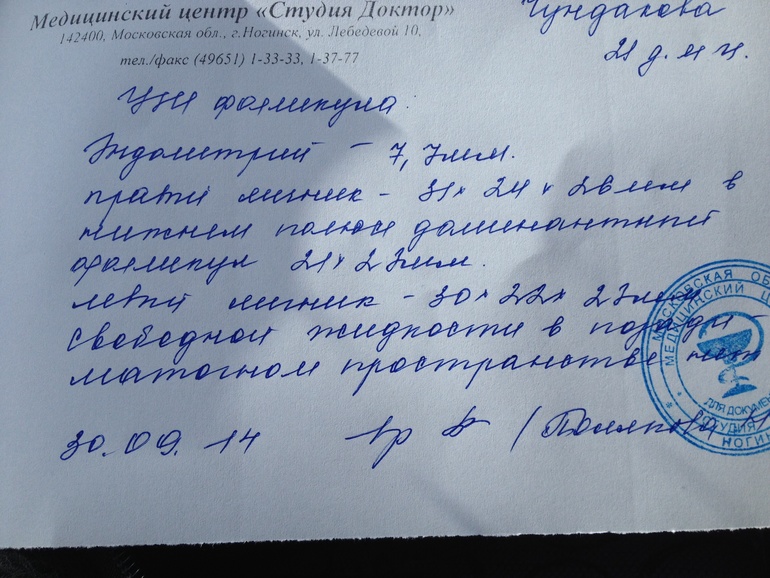

Милые девушки, посмотрите,пожалуйста мое узи. Что скажите? Меня узистка напугала, что левый яичник отдыхает, в правом фолликул, но он может и не лопнуть. Эндометрий очень тонкий, я спросила что может посоветовать,она ответила все к врачу. К нему надеюсь только в субботу попасть. А до субботы я же изведу себя.

буквально сутки до О осталось, эндик кто-то скажет, что на 1-2 мм маловат.. но и с таким везет. А второй яичник отдыхает — так и должно быть. Чаще всего они по очереди.. а у меня второй цикл левй работает, а правый чет и правда отдыхает.